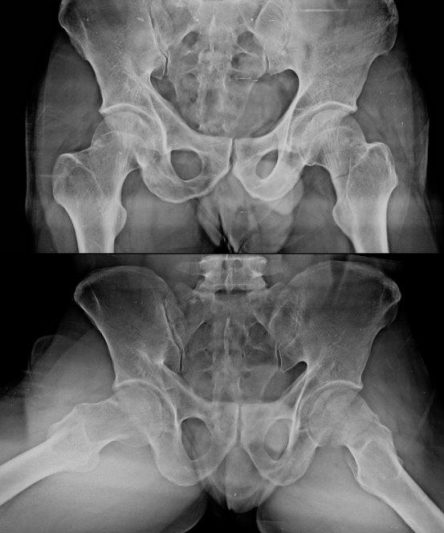

Microskan with Ultra high frequency can take the Lateral Lumbar Spine image of a 90 kg Patient with the correct image receptor

Microskan is the lightest mobile X-ray unit available